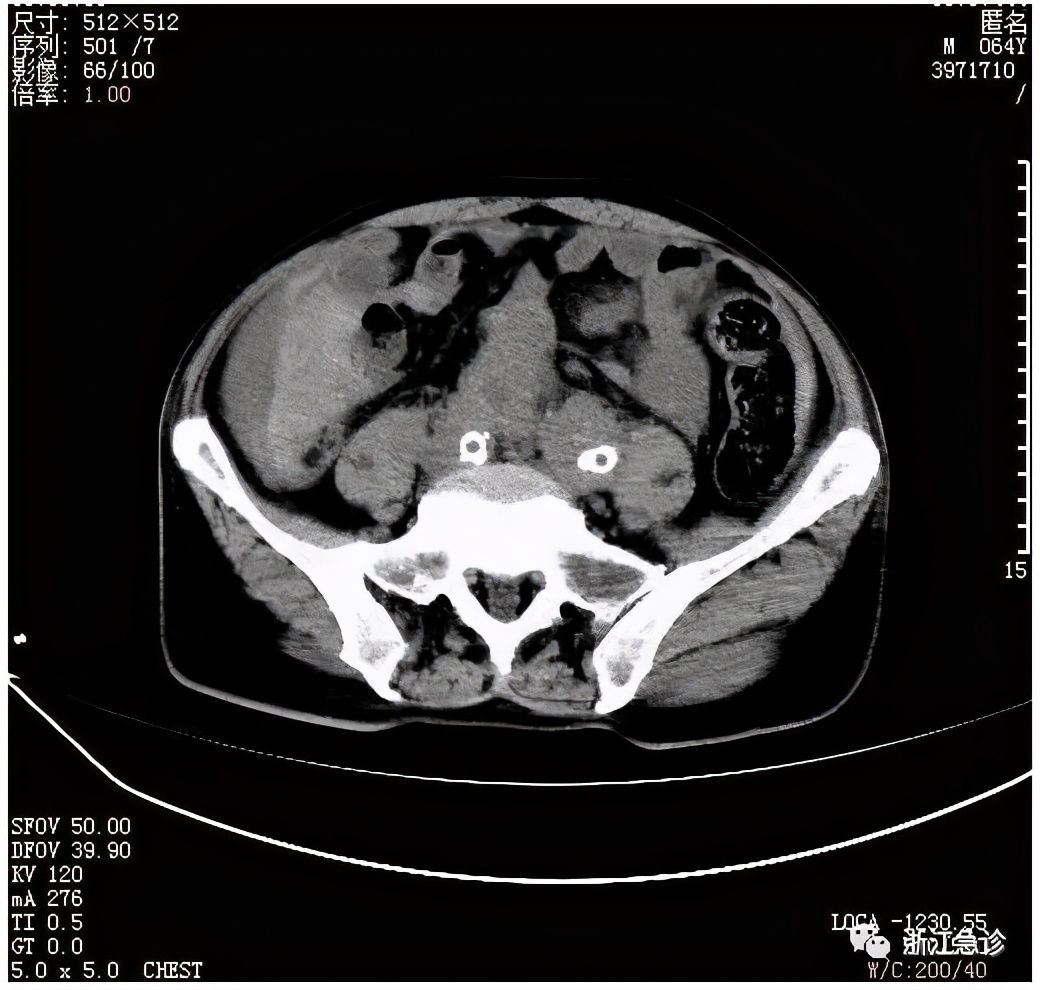

当时,值班医师、住院总医师和三线值班医师经过商量,同样感到一时找不到明确的方向,决定先送重症监护病房抢救,在送去重症监护病房途中,全身做了多个CT(头颅、胸部及腹部CT),终于发现问题所在。

又是夹层脉瘤。

送入重症监护病房后,立即进行超声评估:心胸部超声没有发现明显异常,腹腔有积液,证实了腹部CT的发现。